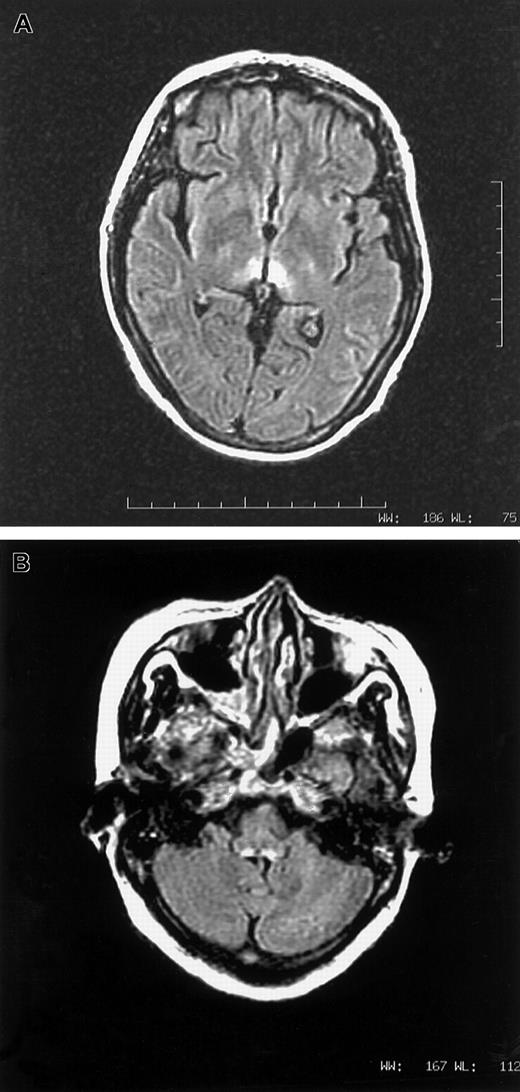

A vegetarian woman, aged 46, with relapsed APL, t(15:17), was given arsenic trioxide 10 mg/d for 28 days. Her first induction with all-trans retinoic acid and daunorubicin a year ago was uncomplicated. Medical history was unremarkable. In particular, there was no prior neurological disorder. Her diet was mainly refined rice and leafy vegetables, very sparse in meat and beans. Starting from day 17, she experienced nausea and vomiting. Pain and congestion were noted over the tongue, throat, and conjunctiva. On day 33, she complained of numbness over lower limbs. Confabulation was absent. On day 37, all 4 limbs were paralyzed and areflexic. Speech was inaudible and bulbar paralysis was noted. She sweated heavily and had a vesicular rash over her body. Cerebrospinal fluid showed white count, 1/μL; protein, 0.5 gm/L; and glucose, 6.7 mM. Studies for Venereal Disease Research Laboratory, bacteria, fungus, virus, and oligoclonal band were negative. Nerve conduction study detected generalized reduction of sensory action potential. Motor conduction was normal, while electromyogram showed active denervation. Drug review did not suggest a neurotoxic side effect from any supportive medication. With cranial magnetic resonance imaging (MRI), lesions consistent with Wernicke syndrome were seen over tectum, periaqueductal gray, and periventricular white matter of the third ventricle, both thalami, and the dorsal medulla (Figure1A,B). The low level of red cell (RBC) transketolase (24 μmol/min L; normal 45-90 μmol/min L), which increased by 32% after in vitro addition of thiamine pyrophosphate, confirmed thiamine deficiency. Parental thiamine 100 mg/d was given. The next day, power of the upper limbs dramatically improved and speech became audible. Over the next 5 days, upper limbs regained full power. As2O3 at 5 mg/d for 28 days as maintenance was given 5 weeks later, with oral thiamine. There was no deterioration in neurology. Lower limb power continuously improved. RBC transketolase during arsenic maintenance was normal, and MRI scan demonstrated complete resolution of all previous abnormalities.

(A,B) MRI images in axial fluid attenuated inversion recovery sequence showing T2-weighted hyperintense lesions surrounding third ventricle (1A) and dorsal aspect of medulla (1B).